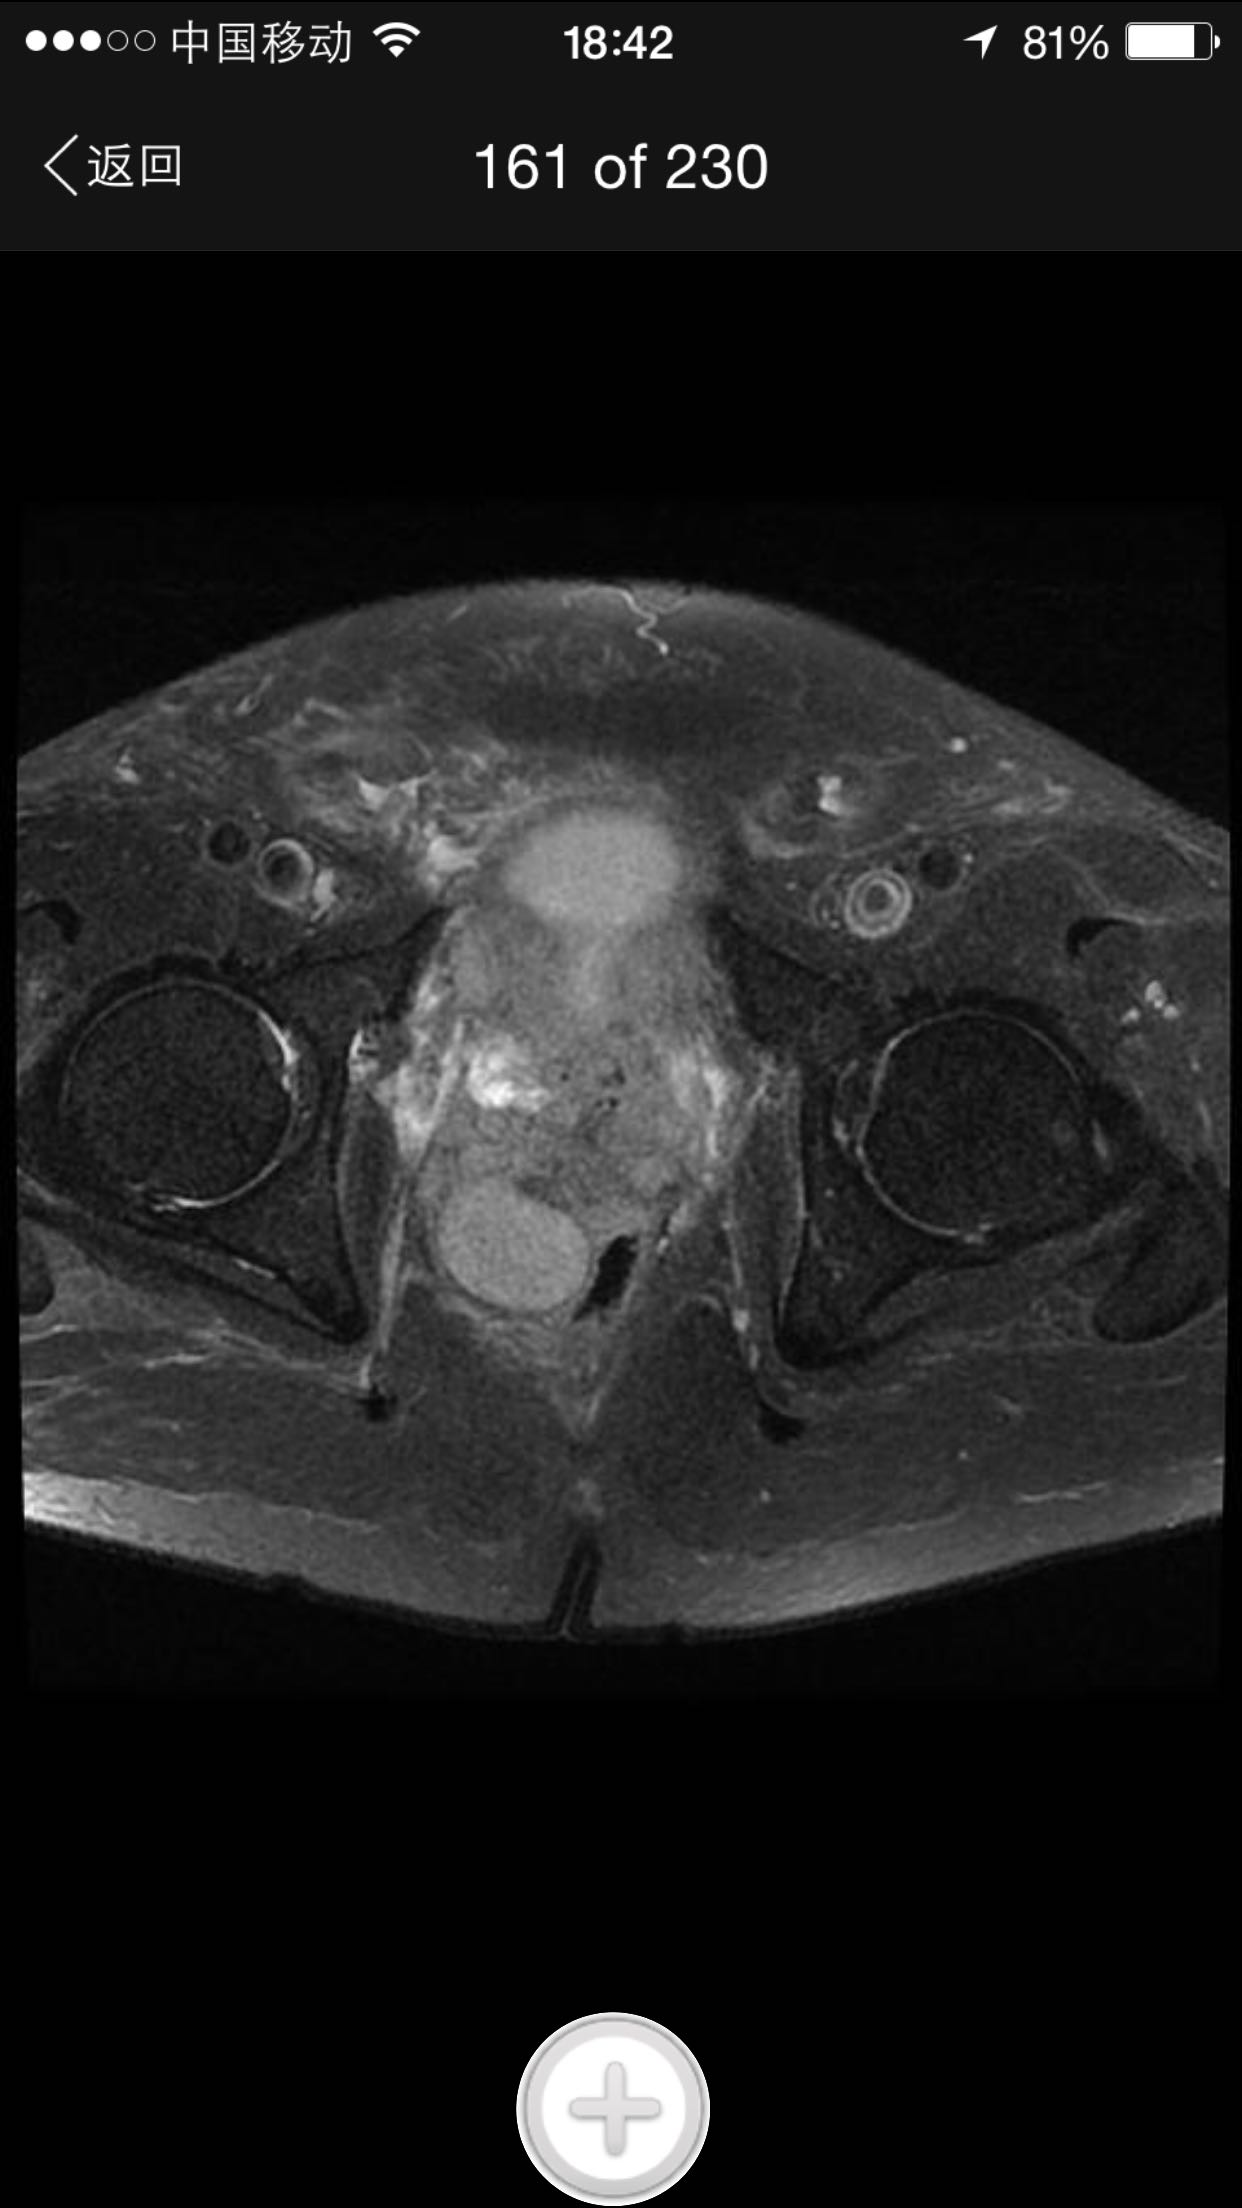

肛诊:前列腺增大,质硬,可扪及多个硬结。 PSA329ng/ml。

诊断:前列腺癌晚期 尿潴留 治疗:考虑患者临床分期较晚,T4期,且淋巴结转移,合并尿潴留,超声提示肾积水,决定行TURP,解决排尿困难。术中快速,如为前列腺癌,直接行手术去势。术中按上述方案处理。术后病理为前列腺中分化腺癌。